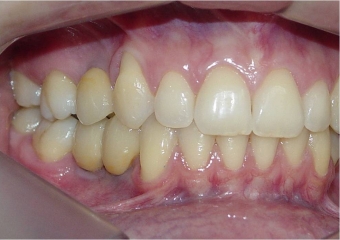

Imagem final

Dentes de porcelana instalados sobre implantes

Sorriso inicial

Sorriso final, do caso terminado em Julho de 2014